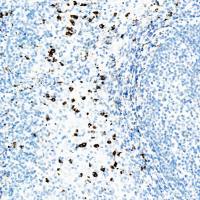

产品名称:MSH2抗体试剂(免疫组织化学)

应用:MSH2是人类错配修复基因家族中一个重要的基因,人类错配修复基因对保持遗传信息的完整性、稳定性及避免遗传突变的产生具有重要作用。突变后该基因缺失,会使细胞错配修复功能缺陷,导致微卫星不稳定(MSI),使肿瘤易感。h MSH2和h MSH6组成的复合体主要识别单个碱基的错配突变和短缺失或插入突变。目前,多和MLH1、MSH6、PMS2共同用于Lynch syndrome的筛查。

阳性部位:细胞核

阳性对照:扁桃体/结直肠癌